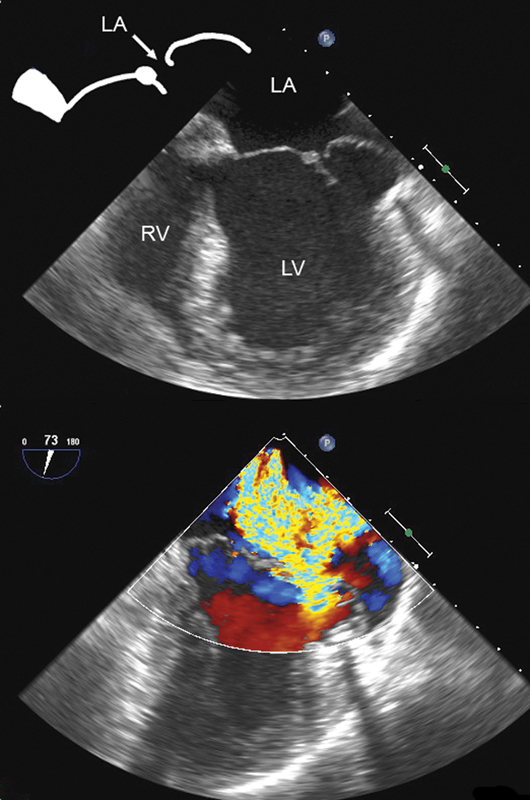

فحوصات تشخيصية لبعض امراض القلب والشرايين التاجية